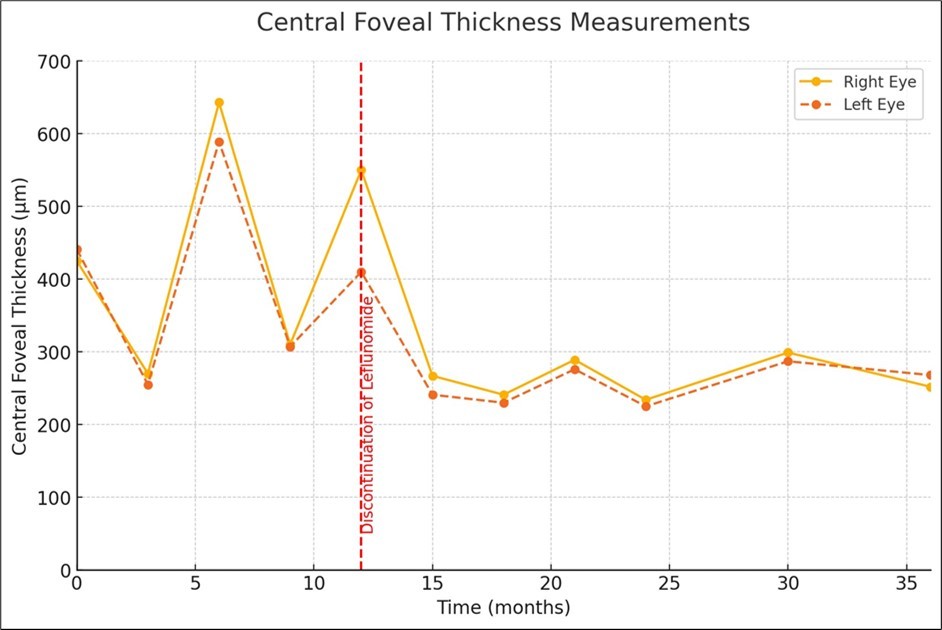

As expected, the central foveal thickness (CFT) measured by SD-OCT exhibited the same pattern of progression over time as the VA, with periods of improvement and partial or total resolution of the CME, followed by relapses of edema when the topical drugs were tapered (Figure 3).

Figure 3.Central foveal thickness measurements before and after discontinuation of Leflunomide.

Notably, the patient had been undergoing Leflunomide therapy for the entire duration of CME remission and relapse, as indicated by the fluctuations in CFT and VA (Figure 2 and Figure 3). Drug-induced CME from other medications was considered, but the temporal association with Leflunomide use and the absence of other known offending drugs supported Leflunomide as the likely cause. Given the history of Leflunomide use and the clinical findings, a multidisciplinary approach was adopted. The Rheumatology department was consulted to discuss the potential link between Leflunomide and CME. Based on their input and a comprehensive literature review, and considering the findings of a previously reported case of bilateral Leflunomide-induced CME, it was decided to empirically discontinue the drug. 3 The resolution of CME upon discontinuation of Leflunomide further substantiated this diagnosis.